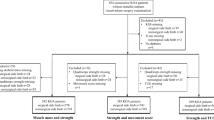

Participants were recruited from a randomized controlled knee joint stabilization trial, involving 159 knee OA patients [27]. Participants were referred to a tertiary rehabilitation center with knee and/or hip complaints due to OA [27]. Of the 159 participants, MRI’s of the knee joint of 94 participants were available for this study. The MRI’s were taken at baseline, prior to the trial. From the included participants, the index knee was imaged, i.e. the knee that most severely affected daily activities based on pain and showed the highest radiographic severity. Inclusion criteria were clinical knee OA diagnosis according to the American College of Rheumatology criteria (knee pain, morning stiffness < 30 min duration, crepitus on active motion, tenderness of the bony margins of the joint, bony enlargement noted on examination, and a lack of palpable warmth of the synovium [28]), age between 40 and 75 years, and written informed consent [27]. Exclusion criteria were total knee arthroplasty, any form of arthritis other than OA, comorbidities that affect daily functioning, severe knee pain (numeric rating scale (NRS) > 8) and contra-indication for MRI (e.g., pacemaker, claustrophobia). Participants were examined by radiologists, rheumatologists and physiatrists. The study was approved by the local Institutional Review Board (29 September 2008, U/2782/0851). The protocol was performed in accordance with the relevant guidelines and regulations.

Descriptive analysis was used for participant characteristics including age, sex, BMI, radiographic severity, the percentage of non-contractile tissue, muscle strength and the GUG time. Normality of data was assessed using the Kolmogorov–Smirnov Test. Data sets of the primary outcome parameters muscle extensor strength and GUG time contained continues measures. The data of the percentage of non-contractile tissue were dichotomized due to skewness of the data into a low-percentage non-contractile tissue group and a high-percentage non-contractile tissue group, based on the median (11.2%), with equal group sizes (n = 47).